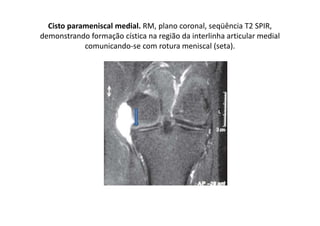

Cisto parameniscal medial. RM, plano coronal, seqüência T2 SPIR,

demonstrando formação cística na região da interlinha articular medial

comunicando-se com rotura meniscal (seta).